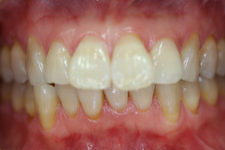

1. 健康な歯ぐき

皆さん定期的に来院していただき、健康な状態を維持されています。歯医者としてもっとも嬉しいケースです。

30代

50代

70代

80代